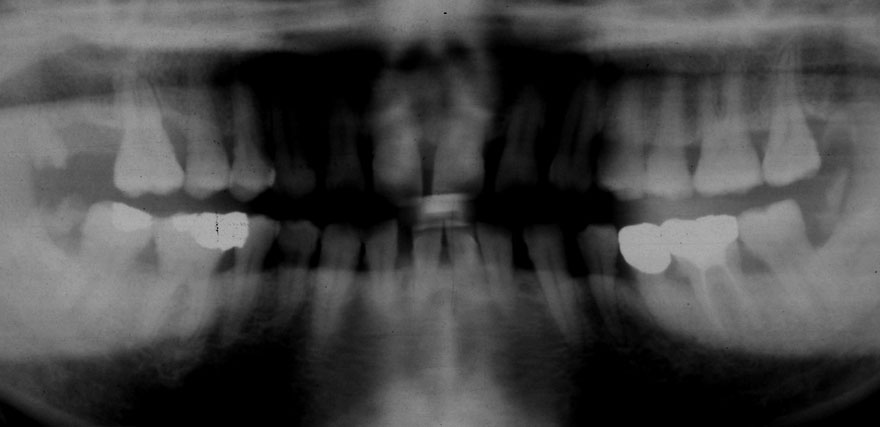

初診時 40歳 女性 平均歯槽骨喪失量:5.24mm

20年後 60歳

平均歯槽骨喪失量:5.79mm

21年間喪失量:-0.55mm

年間喪失速度:-0.027mm

(ケア頻度:1.23ヵ月ごと)